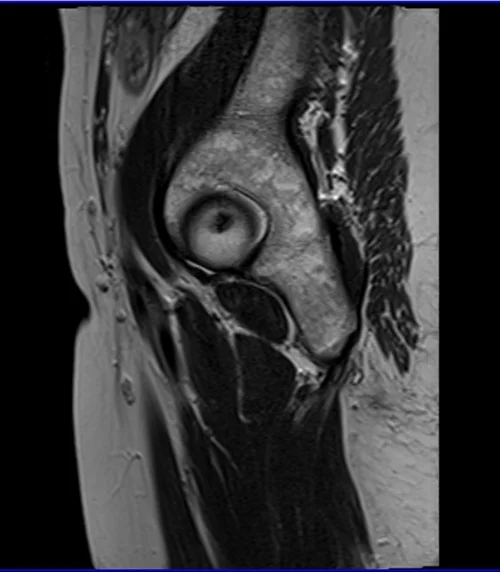

mri hips sag t2 image 2 - MRI